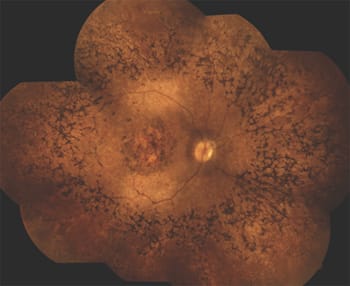

Patient 2 was first seen at the age of six months, after the parents had noted roving eye movements and poor responses to visual stimuli. The funduscopic descriptions in childhood were of normal optic discs, mild attenuation of the vessels and a maculopathy in the presence of a relatively normal periphery. The ERG showed no detectable response. Images of the left eye at 18 years of age are shown in Figure 4.

Figure 4. (A) At the age of 18 years the left fundus of a patient with CRB1 mutations shows a maculopathy and some attenuation of the arterioles. The type of pigmentation is nummular rather than bone-spicule-like. (B) The OCT of the macular area shows a normal foveal depression with an increased retinal thickness surrounding the fovea. Punctate photoreceptor remnants, absence of the outer limiting membrane, and thickened lamination of the inner retina are apparent.

Patient 2 has LCA caused by mutations in the gene encoding CRB1 (Crumbs). CRB1 is localized in Müller glial cells adjacent to the adherens junctions, between Müller glial cells and photoreceptors. Loss of CRB1 function leads to loss of these adhesions and ultimately loss of photoreceptors.7 The CRB1 phenotype shows some characteristic features, but in most cases, only a few of these features are present. Most patients have a short axial length and consequent hyperopia. VA ranges from LP to 20/100.

On initial exam, fundus abnormalities are typically already present, showing attenuated vessels, maculopathy and retinal pigment epithelium abnormalities. Later in life, some, but not necessarily all, of the following features may be present: optic disc pallor with perivascular fibrotic sheathing, attenuated vessels with para-arteriolar sparing of the retinal pigment epithelium (PPRPE), severe maculopathy, and nummular, rather than bone-spicule, pigmentation at the level of the RPE in the periphery. A Coats-like vasculopathy may develop in the periphery. SD-OCTs in patients with CRB1 mutations show increased retinal thicknesses with loss of the outer limiting membrane, which develops during life.8

Such patients also typically show thickened lamination of the inner retina. Therapeutic options are being explored but are still in early phases. An autofluorescence image of a different patient with proven CRB1 mutations and the presence of PPRPE is shown in Figure 5.